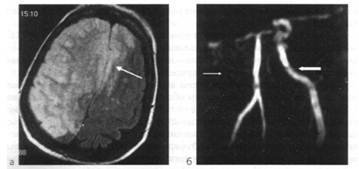

Острый ишемический территориальный инфаркт в бассейне правой внутренней сонной артерии (исследование выполнено через 47 ч от начала заболевания):

а - МРТ головного мозга (аксиальная плоскость, срез на уровне полушарий мозга, Т2TIPM-взвешенное изображение): визуализируется большой гиперинтенсивный очаг инфаркта, занимающий все правое полушарие большого мозга и переднюю часть лобной области противоположного полушария (показано стрелкой); б - МРА магистральных сосудов головного мозга: выявлена окклюзия правой внутренней сонной артерии, о чем свидетельствует отсутствие MP-сигнала (показано тонкой стрелкой), левая внутренняя сонная артерия определяется четко (показано толстой стрелкой)